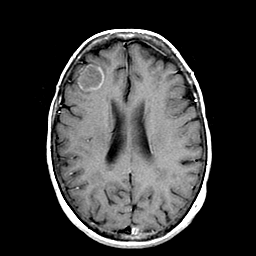

Metastatic Adenocarcinoma of the Colon: T1-weighted MR -- Slice #15

[Home][Help][Clinical] Slice 15